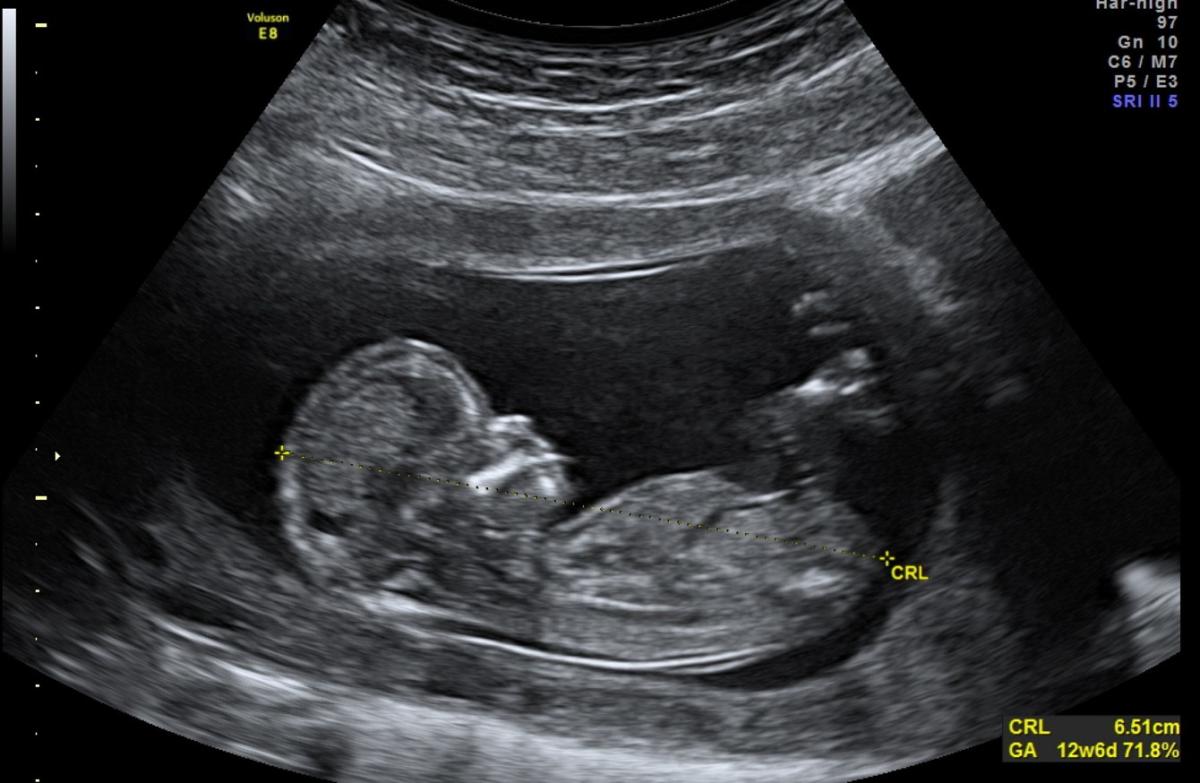

Gebelik sürecinin, sağlık personeli veya kurumu tarafından izlenmesi gerektiğini aktaran Dr. Baran, “İlk üç ay, gebelik kayıplarının görülme ihtimali daha yüksektir. Bu dönemde, anne adayları bebek hareketlerini henüz hissedemediği için daha endişeli olabiliyor. Sağlıklı gebelik takibi, ilk üç ay süresince 2-3 hafta arayla yapılmaktadır. Hekimle gerçekleşen her görüşmede tansiyon ve kilo ölçülerek, gerekli tahliller yapılacak. Bebeğin kalp atışlarıyla büyüklüğü ise ultrasonla değerlendirilecektir. Vajinal kanama, vajinadan su gelmesi, rahimde kasılmalar görülmesi, bebek hareketlerinde azalma gibi belirtiler görülmesi durumunda acilen hekime gidilmesi gerekiyor.” ifadelerini kullandı.